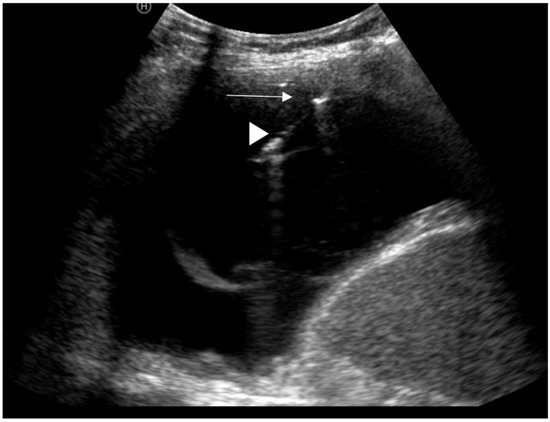

13. Ultrasound